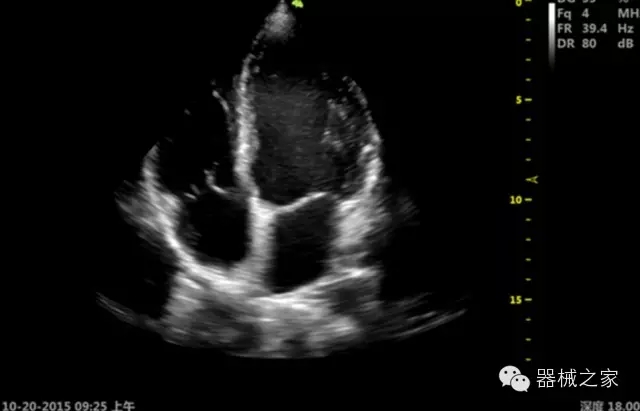

臨床圖片賞析

·ICU/CCU;

·飛依諾特有心臟純凈波探頭提供更好的穿透力和彩色敏感度,以及結(jié)合TView梯形拓展改善困難病人深部組織成像;

·獨有RF敏感血流使得心臟血流完美呈現(xiàn);